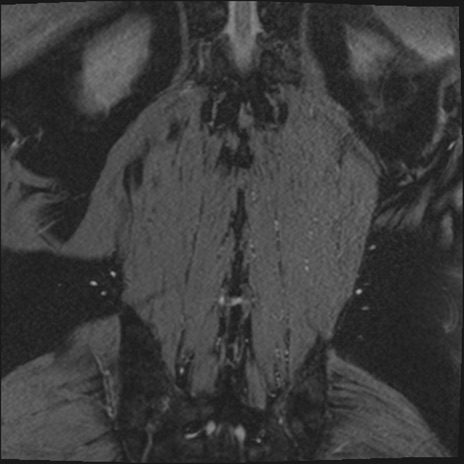

【整形】TIPS症例2 腰椎MRI 3D(冠状断像)

【症例】70歳代男性

【主訴】左下肢痛

【現病歴】2週間前くらいから腰痛、左下肢痛あり。左臀部から大腿、下腿外側のしびれが常時ある。歩行とともに同部位の痛みあり。

【身体所見】Lasegue70-/60+、Bragard-/±、PTR ±/±、ATR -/-、IP 5/5、TA 5/4、TS 5/5、EHL 右第1足趾なし/3、FHL 5/5、hypersthesia(-)、足背動脈触知良好

異常所見と診断は?